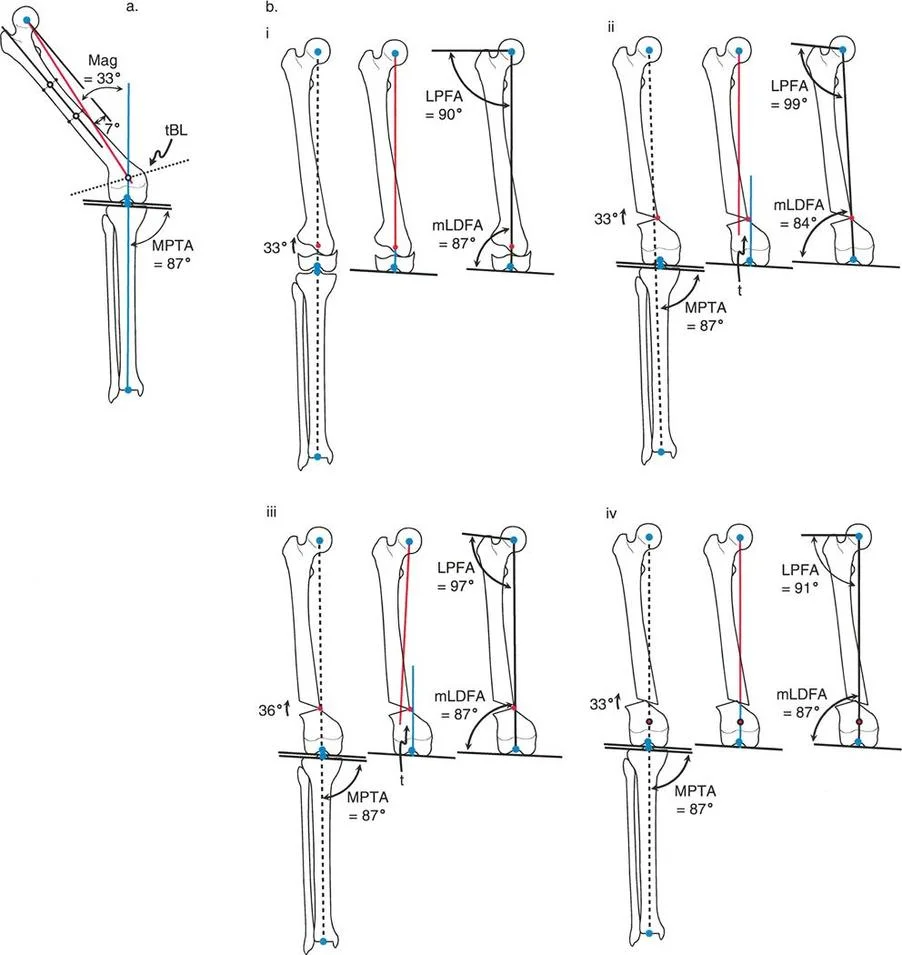

- mLDFA (mechanical Lateral Distal Femoral Angle) This is the lateral angle formed between the mechanical axis of the femur and the distal femoral joint line. The normal value is 87 degrees, with a standard range of 85 to 90 degrees. An mLDFA greater than 90 degrees indicates a distal femoral varus deformity. An mLDFA less than 85 degrees indicates a distal femoral valgus deformity.

- LPFA (Lateral Proximal Femoral Angle) This is the lateral angle formed between the mechanical axis of the femur and a line drawn from the tip of the greater trochanter to the center of the femoral head. The normal value is 90 degrees (range 85 to 95 degrees).

- MPTA (Mechanical Proximal Tibial Angle) This is the medial angle formed between the mechanical axis of the tibia and the proximal tibial joint line. The normal value is 87 degrees (range 85 to 90 degrees). An MPTA less than 85 degrees indicates proximal tibial varus. An MPTA greater than 90 degrees indicates proximal tibial valgus.

The Center of Rotation of Angulation (CORA) represents the apex of the deformity. To find the CORA, the surgeon draws the Proximal Mechanical Axis (PMA) line and the Distal Mechanical Axis (DMA) line.

* The PMA is drawn by taking the normal joint orientation angle from the proximal joint and extending a line down the shaft.

* The DMA is drawn by taking the normal joint orientation angle from the distal joint and extending a line up the shaft.

* The exact point where the PMA and DMA intersect is the CORA.

Osteotomy Rule One Pure Angulation

When the osteotomy line and the ACA both pass directly through the CORA, pure angular correction is achieved.

The Biomechanical Result

Osteotomy Rule Two Angulation with Translation

When the ACA passes through the CORA, but the osteotomy line is made at a different level (either proximal or distal to the CORA).

The Biomechanical Result

The mechanical axis and joint orientation angles are perfectly restored. However, because the bone cut is made at a distance from the hinge point, the bone segments will mathematically translate relative to one another. This creates a visible "bump" or step-off in the anatomic axis. While the bone looks jagged on an x-ray, the load-bearing mechanical axis is flawless.

Osteotomy Rule Three Secondary Deformity

When the osteotomy line and the ACA are both placed at a level different from the CORA.

The Biomechanical Result

A secondary translational deformity is created. While the angular deformity may appear to be corrected, the mechanical axis will not be fully restored. The proximal and distal mechanical axes will be parallel but not collinear, resulting in residual Mechanical Axis Deviation (MAD).

The Opening Wedge Osteotomy Sequence

- Biomechanics and Limb Length The opening wedge inherently lengthens the limb. The ACA is placed on the convex side of the deformity (the side that acts as the hinge).

The Closing Wedge Osteotomy Sequence

- Biomechanics and Limb Length The closing wedge inherently shortens the limb. The ACA is placed on the concave side of the deformity.

Juxta Articular Deformities

Deformities located very close to the joint line present a unique challenge. The CORA is often located within the epiphysis or the joint space itself.

- Surgical Pearl You cannot cut through the CORA in these cases. You must utilize Paley's Rule 2. Place your hinge (ACA) at the joint line (the CORA), and perform your osteotomy in the metaphyseal bone.